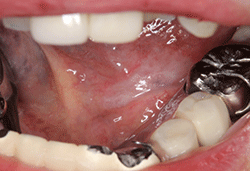

MTXを減量、プレドニゾロンは8mgに増量された。その結果、3週間後には潰瘍は上皮化し、痛みも消失した(図❷)。

図❷ MTXの減量後3週間で潰瘍は上皮化した